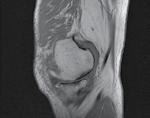

Figura 1: Cazul unei femei de 66 de ani, cu probleme de sănătate complexe, care a suferit o fractură patologică la nivelul humerusului din cauza unei metastaze. (A) Evidențiază metastaza osteolitică din humerus. (B) Imagine scintigrafică ce arată răspândirea sistemică. (C) Imagine postoperatorie care prezintă o tijă centromedulară utilizată pentru osteosinteză, permițând mișcarea imediată a brațului.